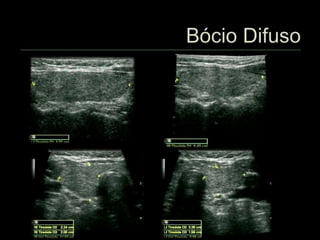

 Bócio é o aumento do volume da tireóide

 Independente da causa

 Bócio difuso

 Tóxico

 Atóxico

 Hiperplasia difusa

 Causas

 Déficit de ingestão de iodo (bócio endêmico)

 Distúrbios da hormonogênese (formas familiares)

 Drogas que interferem na absorção do iodo

(lítio, cobalto, iodatos, fenilbutazona)

 Induzido por alimentos

(repolho, soja, amendoim, pêssego, morango, espinafre,

rabanete)